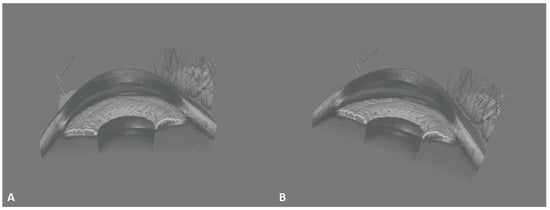

The acquisition efficiency of SS-OCT is tremendously improved over that of SD-OCT. That ultrafast speed, together with efficient horizontal and longitudinal scanning, enables the creation of 3D images, as displayed in Figure 9. It allows for a more intuitive and stereoscopic view of the positional relationships between the structures of the anterior segment. The 3D imaging of the anterior segment may greatly improve ophthalmic imaging diagnosis for conditions such as intraocular lens implantation (Figure 10) and anterior chamber space-occupying lesions. Anterior 3D-OCT is helpful in enabling precise customization in refractive surgeries, cataract intraocular lens implantation, and assessing the anterior angle and aqueous outflow for glaucoma diagnosis and monitoring [].

Figure 9.

These 400-kHz SS-OCT images demonstrate the normal three-dimensional (3D) anterior segment morphology. (A) Frontal view of sagittal plane; (B) oblique view of sagittal plane. Iris folds, the anterior chamber angle, and the corneoscleral limbus are clearly visible.

Figure 10.

These 3D, 400-kHz SS-OCT images demonstrate an eye with an intraocular lens (IOL) with a small pterygium on the nasal side. (A) The structural relationship between the IOL and the iris is clear. (B) The frontal view. (C) The side view, in which the entire side of the iris is clearly visible (white arrow), as well as the lower interface of the IOL.